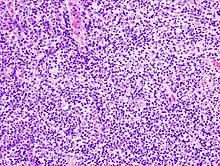

Lymphoproliferative disorders (LPDs) refer to a specific class of diagnoses, comprising a group of several conditions, in which lymphocytes are produced in excessive quantities. These disorders primarily present in patients who have a compromised immune system. Due to this factor, there are instances of these conditions being equated with "immunoproliferative disorders"; although, in terms of nomenclature, lymphoproliferative disorders are a subclass of immunoproliferative disorders—along with hypergammaglobulinemia and paraproteinemias.

Lymphoproliferative disorders are a set of disorders characterized by the abnormal proliferation of lymphocytes into a monoclonal lymphocytosis. The two major types of lymphocytes are B cells and T cells, which are derived from pluripotent hematopoietic stem cells in the bone marrow. Individuals who have some sort of dysfunction with their immune system are susceptible to develop a lymphoproliferative disorder because when any of the numerous control points of the immune system become dysfunctional, immunodeficiency or deregulation of lymphocytes is more likely to occur. There are several inherited gene mutations that have been identified to cause lymphoproliferative disorders; however, there are also acquired and iatrogenic causes.[2]